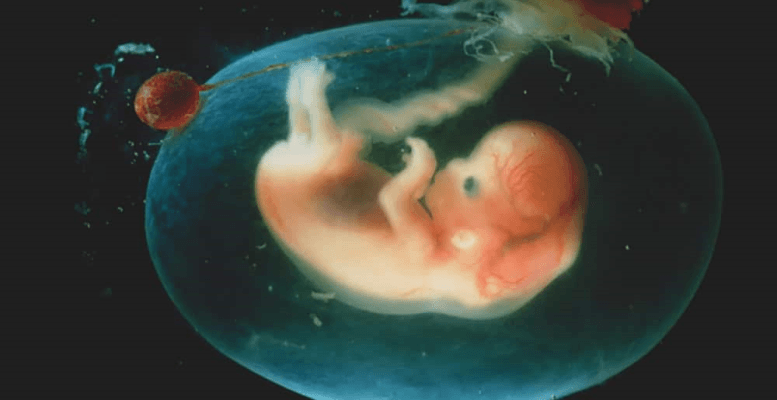

Gebelik durumunda bebeğinizin rahmin içinde büyür. Hamileliğin 12. gününden sonra hamilelik, bebek kesesi de denilen rahmin içinde oluşmaya başlar. Kese içerisinde bebeğinizi 5 ila 7 hafta sonrasında görmeniz mümkün. Bu bebek kesesine amniyon kesesi de denir.

Bu sıvı oldukça berrak olmakla beraber hafif sarı tonlarında bir renge sahiptir. İşlevi bakımından fetüsü sarmakla görevlidir. Bebek bu sıvının içerisinde bulunur ve fetüsün büyümesi konusunda düzen ve yaşam için oldukça önemlidir. Hamilelikte ilk 4 ay sonrasında fetüsün böbrekleri oluşmaya başlar. Bu da fetüsün idrar çıkarma işlemini yapmasına olanak sağlar. Fetüs bu sıvıyı içebilmektedir. İçtikten sonra da sindirebilir ve yeniden idrarını da bu sıvının içerisine yapabilir. Zaman içerisinde bu sıvı tamamıyla fetüsün idrarı olmaya başlar.

Sadece idrar değil, idrarla birlikte bu sıvının içerisinde hormonlar, besin maddeleri ve antikorlar da bulunmaktadır. Rahim içerisinde duran bebek bu sıvı ile çevrilmektedir. Bebeğin güvende olmasını ve oluşabilecek zararlara kaşı korunmasını sağlar. Bebeğinizin ihtiyaç duyduğu tüm gerekli besinleri içerisinde bulundurduğundan bebeğinizin sağlığı açısından oldukça büyük önem taşır.

Bebek kesesi içerisinde bulunur ve fetüsü çeşitli zararlara karşı korur. Fetüsün gelişimi açısında oldukça büyük önem taşır. Bu sıvı içerisinde bol miktarda protein, yağ, karbonhidrat ve fosfolipid bulundurur. Renk bakımından berraktır ve hafif sarı tonlara sahiptir. Bebeğiniz bu sıvının içerisinde yüzer. Döllenmiş yumurtanın rahim duvarına yapışması ile oluşmaya başlar. Durgun bir sıvı değildir. Bunun nedeni sıvının içerisinde olan fetal hareketler, anne hareketleri ya da yutkunma, soluma gibi durumlardır.

Fetüsün düzgün bir biçimde gelişmesini sağlar. Bunun yanında vücut sıcaklığı korur ve anneye ani hareketler nedeniyle fiziksel baskısının uygulanmasını engeller. Miktar bakımından çok az ya da çok fazla olması tehlikeli bir durumdur. Çok az olduğu durumlarda fetüsün gelişmesinde engelleyici etki oluşturur. Gerekenden fazla miktarda olması ise doğuştan gelen sorunlara yol açabilmektedir.